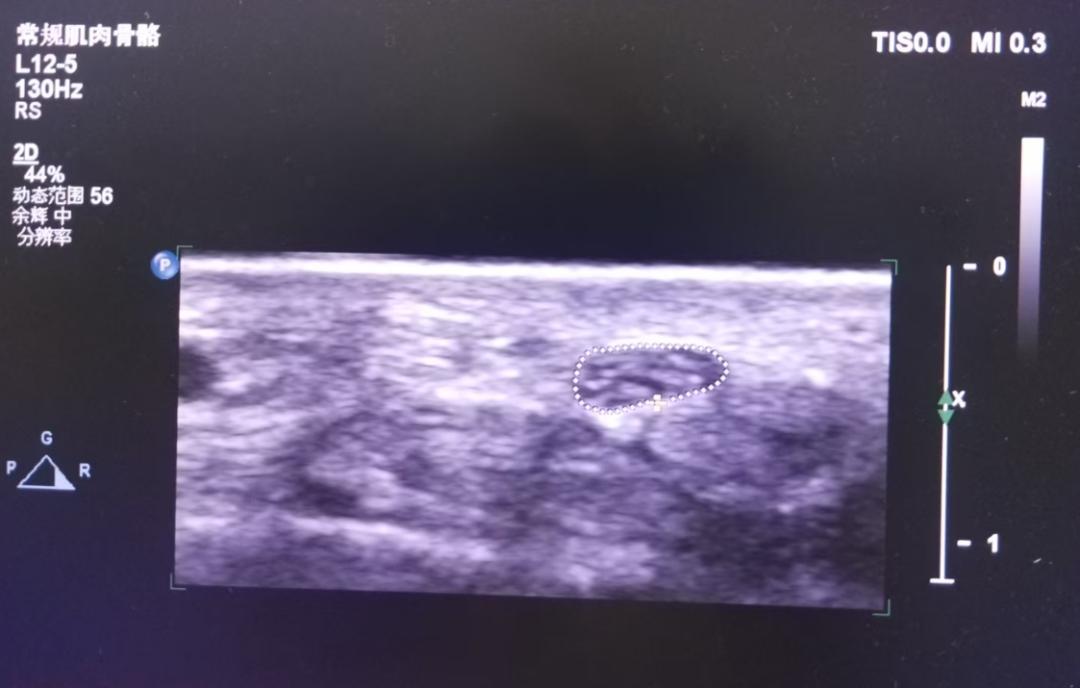

接诊医生详细询问了大姨的病情,并进行了全面的检查。在排除了其他可能的原因后,医生建议大姨进行超声检查。超声科主任毕晓芳利用肌骨超声对大姨的手腕部进行了精准检查,通过超声动态成像技术,清晰观察到:

✓ 腕管内神经水肿信号

✓ 肌腱滑动受限轨迹

✓ 局部炎性渗出情况

腕横韧带增厚压迫正中神经(腕管综合征)

拇长展肌腱鞘腔隙狭窄(桡骨茎突狭窄性腱鞘炎)